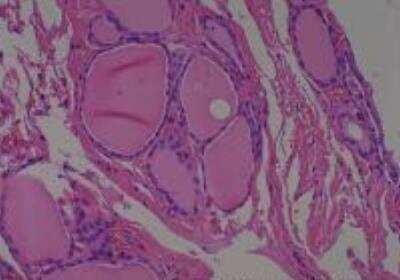

Scientific Data Images for Human Multi Tissue MicroArray (Normal Adjacent)

Hematoxylin & Eosin Stain: Human Common Tissue MicroArray (Normal Adjacent) [NBP2-30215] - 102. Stomach